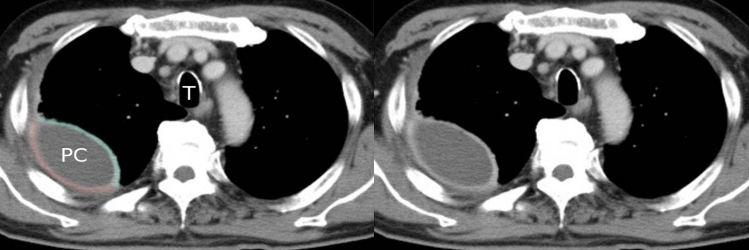

The split-pleura sign z

refers to thickening and contrast enhancement of the parietal and visceral pleurae separated by empyema or exudative effusion. The sign is considered reliable in distinguishing empyema from lung abscess.

Lung abscesses, furthermore, tend to be **round in contrast to the lenticular shape typical of empyemas.

CT chest (with contrast; axial plane; mediastinal window)

-

CT scan shows right-sided pleural fluid collection (PC). The collection has a lenticular (biconvex) shape and is accompanied by thickening of the adjacent parietal (red line) and visceral pleurae (green line).